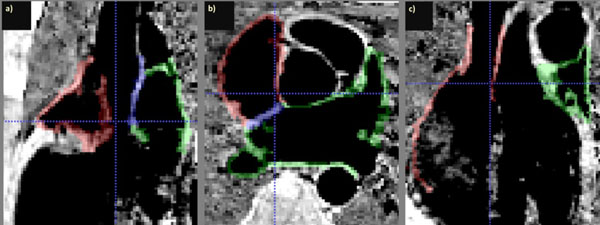

Blood signal was strongly attenuated in relation to the myocardium, allowing the reconstruction of both the epi- and endocardial surfaces from the PSIR images (Fig. 1). The measured atrial wall thickness for each subject is mapped onto the epicardial surface and shown in Fig. 2. Wall thickness was on average 3.01 ± 1.09 mm (range: 2.80 ± 1.05 to 3.32 ± 1.16 mm), in good agreement with post-mortem data. The distinctive atrial bundle of the crista terminalis is clearly visible as a ridge with increased thickness and the pulmonary vein sleeves are thinner than other regions of the atria.

Figure 1.

a) Sagittal, b) transverse and c) coronal images of the atria, overlaid with the atrial wall segmentation. Red: right atrial wall, green: left atrial wall; blue: septum.